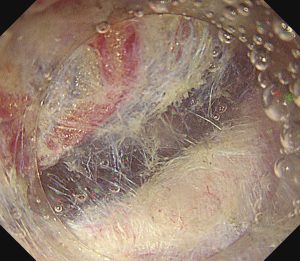

重症急性膵炎後のWONに対するEUS下膿瘍ドレナージ